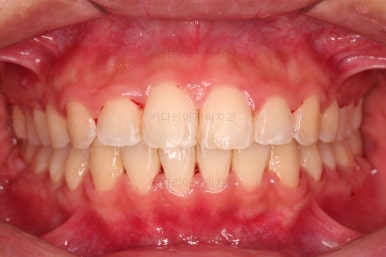

5. 마무리와 치료 종료

마무리가 잘 되었습니다.

큰 문제는 없었지만, 약간 삐뚤었던 치열이 가지런하게 정렬이 잘 되었고요.

맞물림도 매우 좋고, 뻗친 앞니 각도도 매우 좋아졌습니다.

입 안의 모습만 보면 최상급의 마무리가 되었고요.